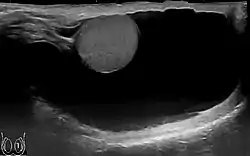

Scrotal ultrasound of a 10 cm large hydrocele, with anechoic (dark) fluid surrounding the testicle.